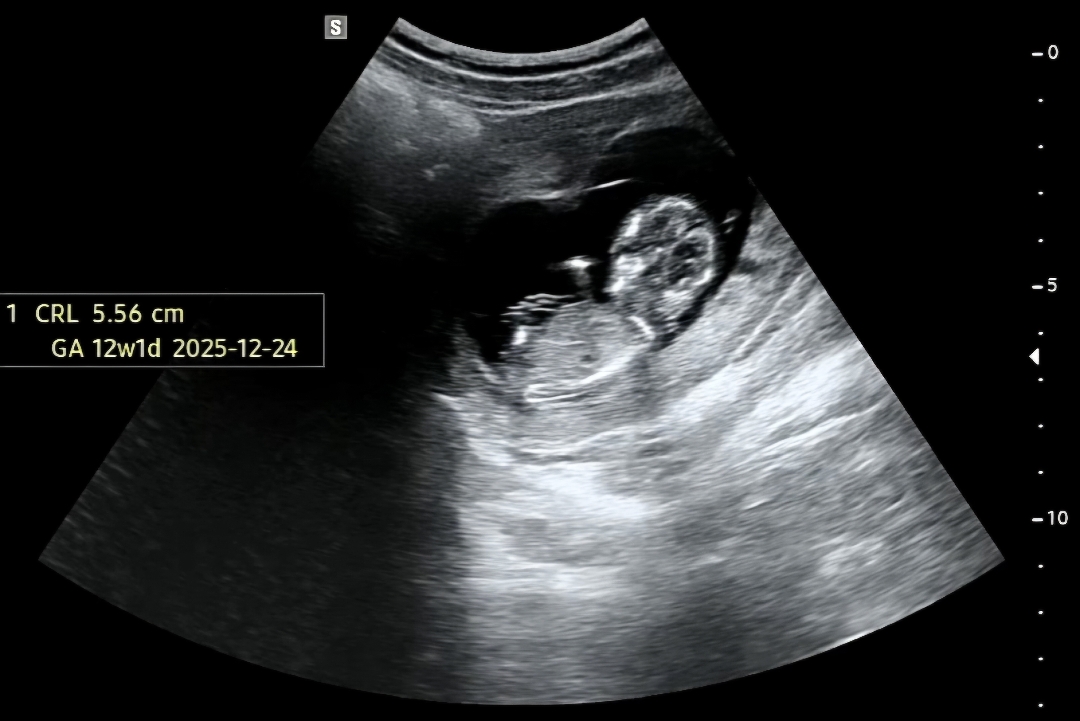

12주 1일입니다! 아들일까요?! 딸일까요?! 개입 한번 부탁드려요